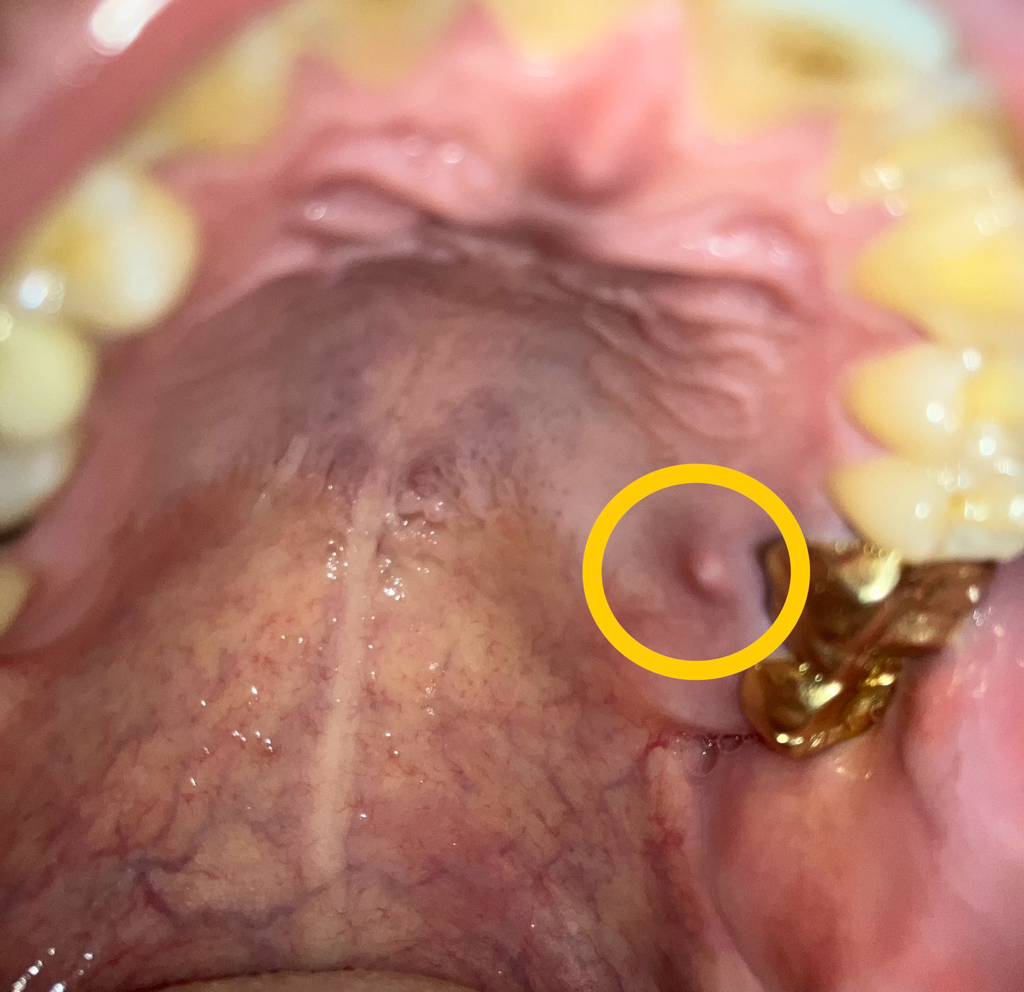

치아내부의 신경관에 감염이 생기게 되면 치아의 뿌리 끝에 고름이 차게 되고 시간이 지나면서 잇몸밖으로 나오게 됩니다.

이런경우에는 해당치아를 신경치료해서 염증을 줄일수 있습니다.

아마도 치아 뿌리끝에 염증이 생긴거 같습니다. 신경치료를 해야될수도 잇으니 치과에 가셔서 검진을 받아보세요.

잇몸에 염증이 생긴 상태입니다. 염증이 어디서 비롯되었는지를 먼저 파악해야 합니다. 만약 잇몸에서 비롯되었다면 잇몸치료를, 치아의 신경(치수)에서 기원한 염증이라면 어느 치아인지 먼저 파악해야하고 그 다음 필요하다면 신경치료를 진행합니다. 주변 크라운으로 씌운 치아가 신경치료가 안되어 있다면 크라운을 뜯고 신경치료를 해줍니다. 신경치료가 이미 되었다면 재신경치료 또는 치근단절제술을 시행하게 됩니다.